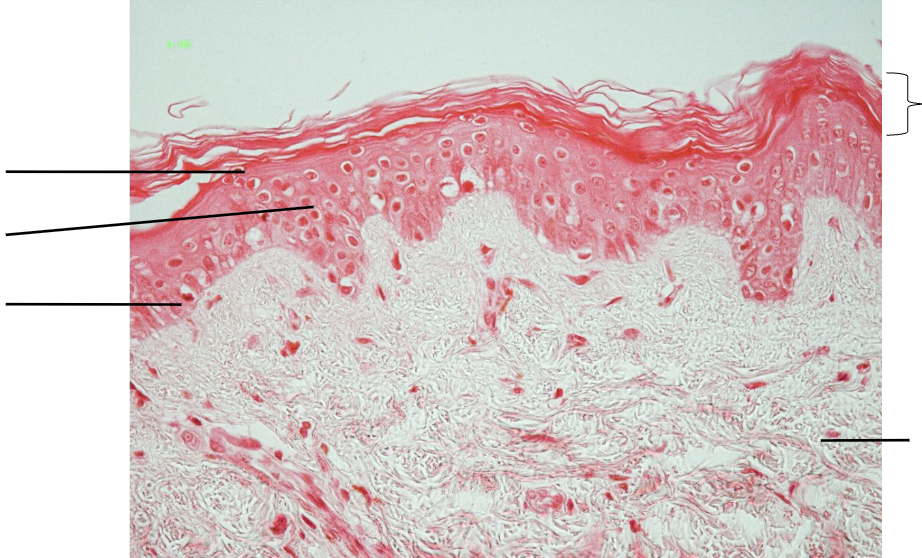

Label

Thin skin